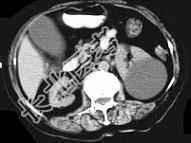

- 多项选择题女,38岁, 左腰部胀痛不适,CT平扫+增强如图所示, 下列说法正确的是 ( )

A、平扫时可见左肾一类圆形囊性病灶

B、病灶边界清晰,表面光整

C、增强扫描皮质期和实质期该病灶均未见强化

D、考虑为左肾囊性肾癌

E、考虑为左肾囊肿